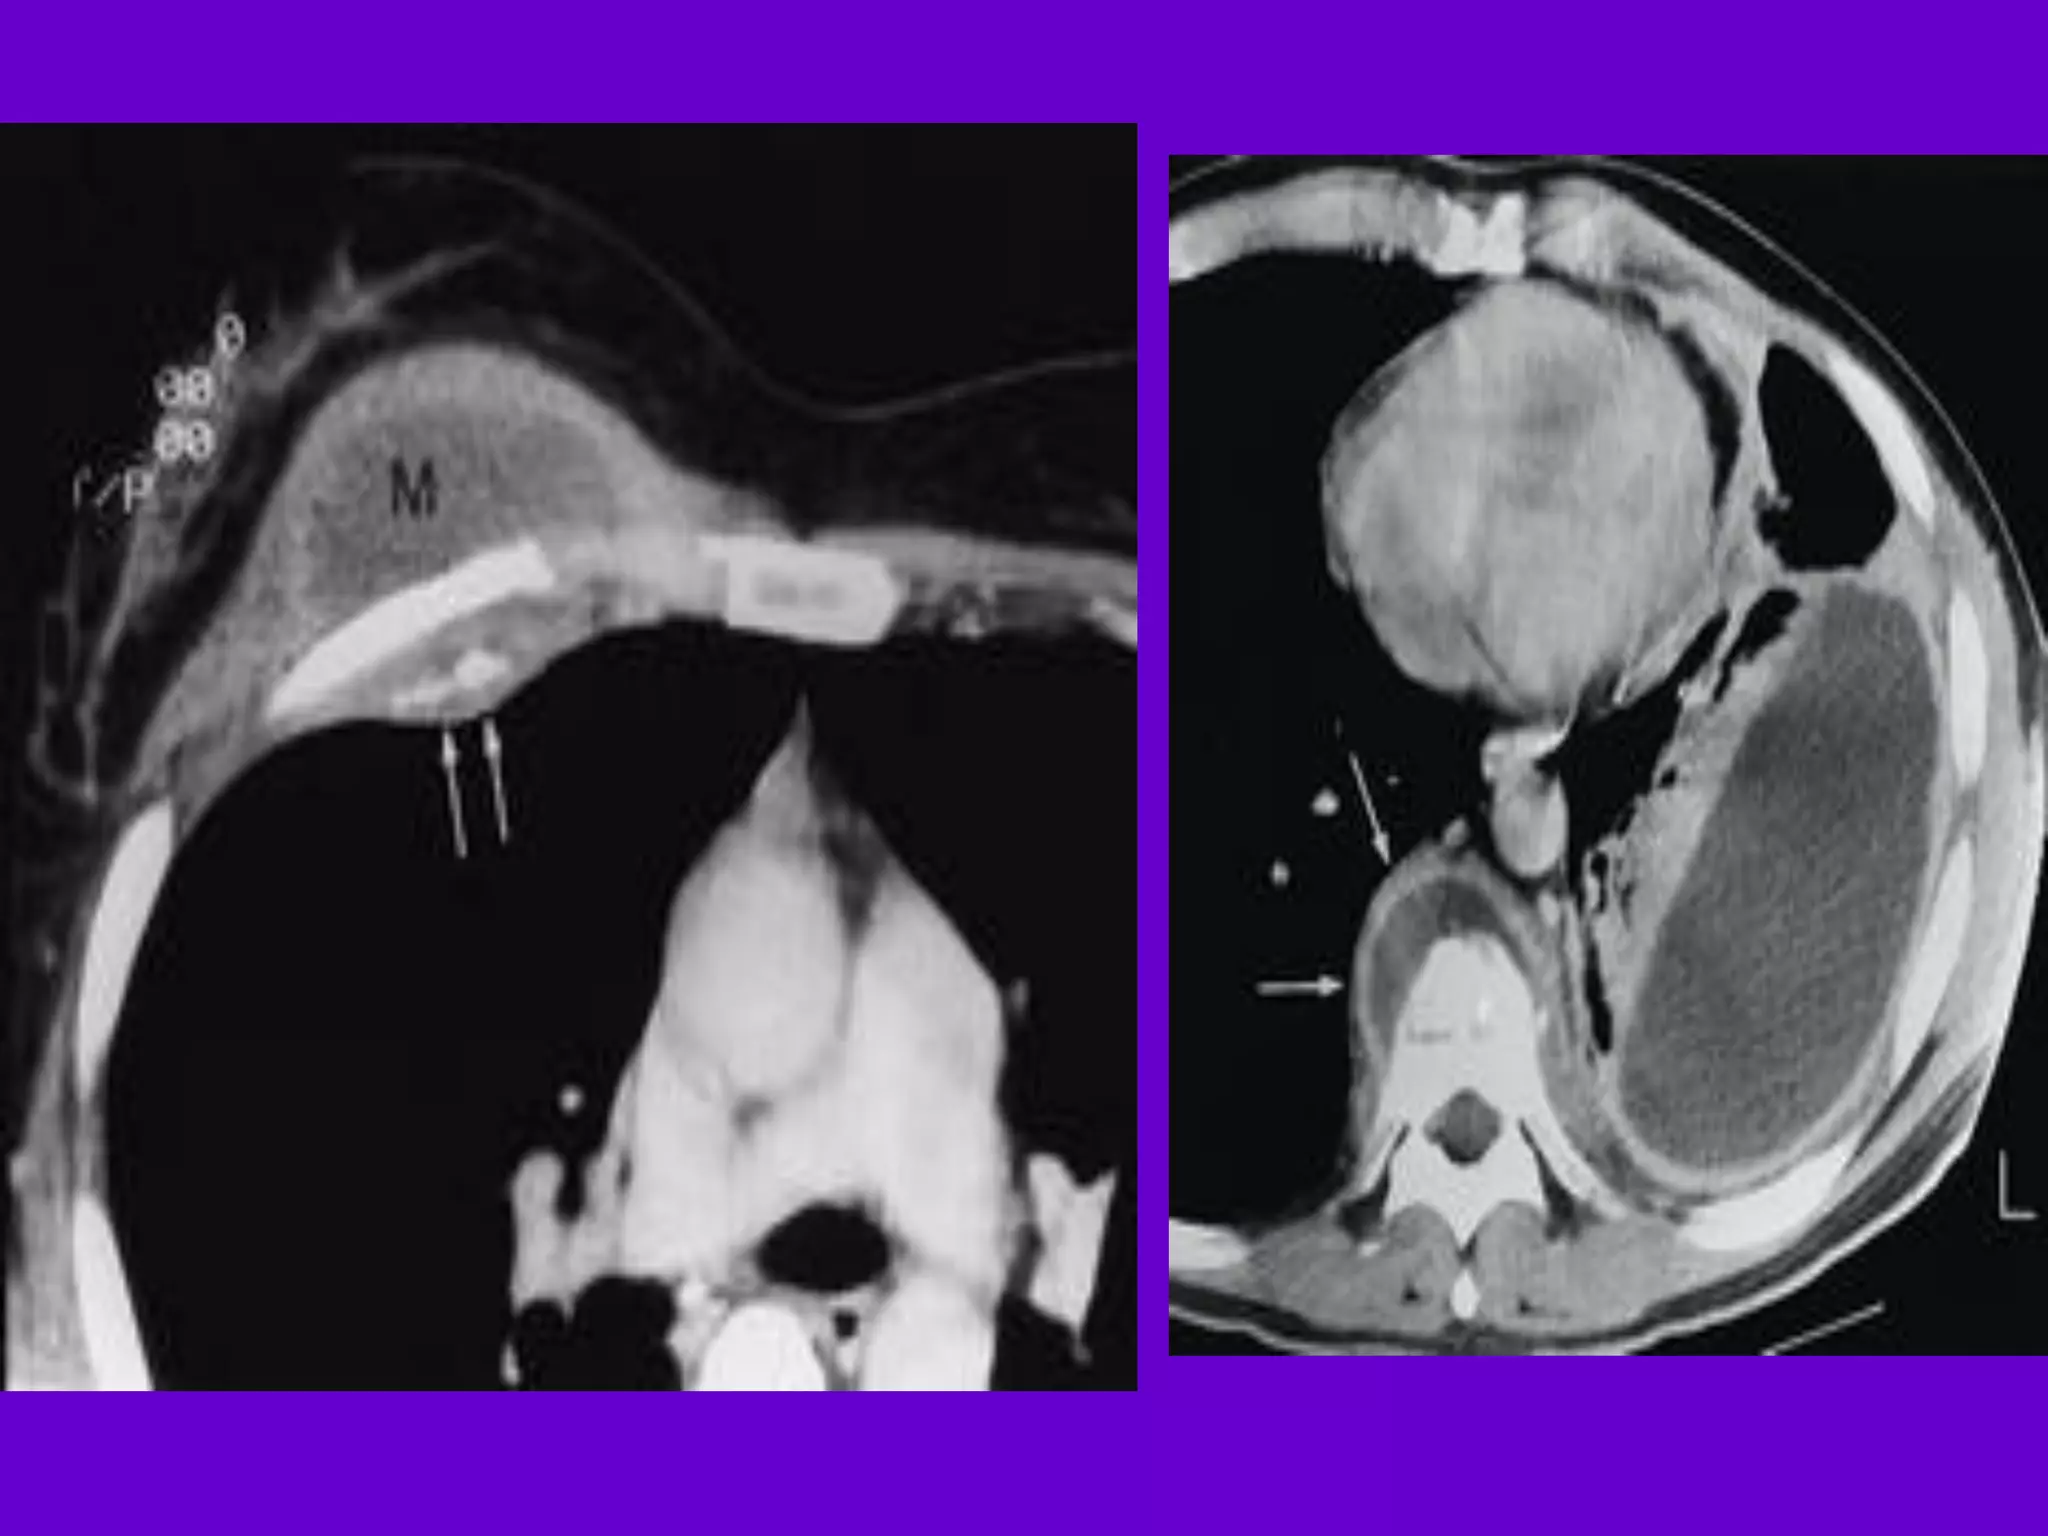

Pulmonary TB :

Lobar Pneumonia

􀂄

CT is superior than plain CXR in picking

up the

consolidation, atelectasis and the hilar LN

thereby

making the diagnosis easy.

􀂄 MRI reveals some of these changes,

however, CT is

the diagnostic modality of choice in such

cases.

Bronchopneumonia

On CT it is usually B/L and widespread,

not always

symmetrical involvement of lungs.

Hilar and Mediastinal

Lymphadenopathy

CT and MRI depict the hilar and

mediastinal LN

equally well.

􀂄 Calcification in the nodes is however

better seen on

CT.

􀂄 Necrosis is seen as focal areas of low

attenuation on

a CECT.

􀂄 On MRI focal necrosis is seen as areas

of increased

signal intensity on T2W images.

Skeletal TB

Pott’s Disease (vertebral TB)

CT and MRI helps in demonstrating a

small focus of

vertebral body involvement and defining

the extent of

the disease.

􀂄 CT/MRI help to evaluate TB involving

the craniovertebral

junction, sacro-iliac joint and posterior

appendages.

􀂄 They are also helpful in assessment of

spinal canal

encroachment , posterior element

involvement and in

deciding the surgical approach.